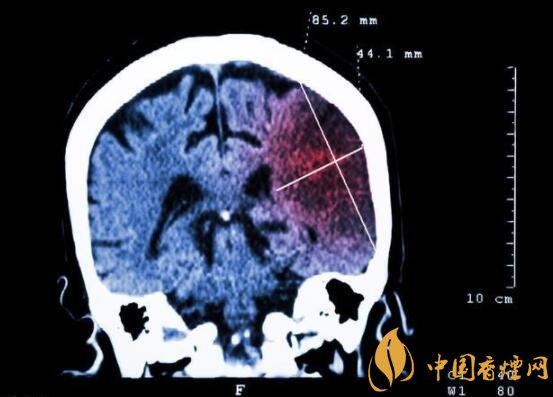

一般而言,急性腦梗塞與長期吸煙有非常密切的聯(lián)系。有長期煙齡遇到肢體活動(dòng)不順,做頭顱核磁共振檢查往往查出一側(cè)大腦中動(dòng)脈閉塞的可能性很高。由此可見,吸煙確實(shí)與中風(fēng)存在一定聯(lián)系。